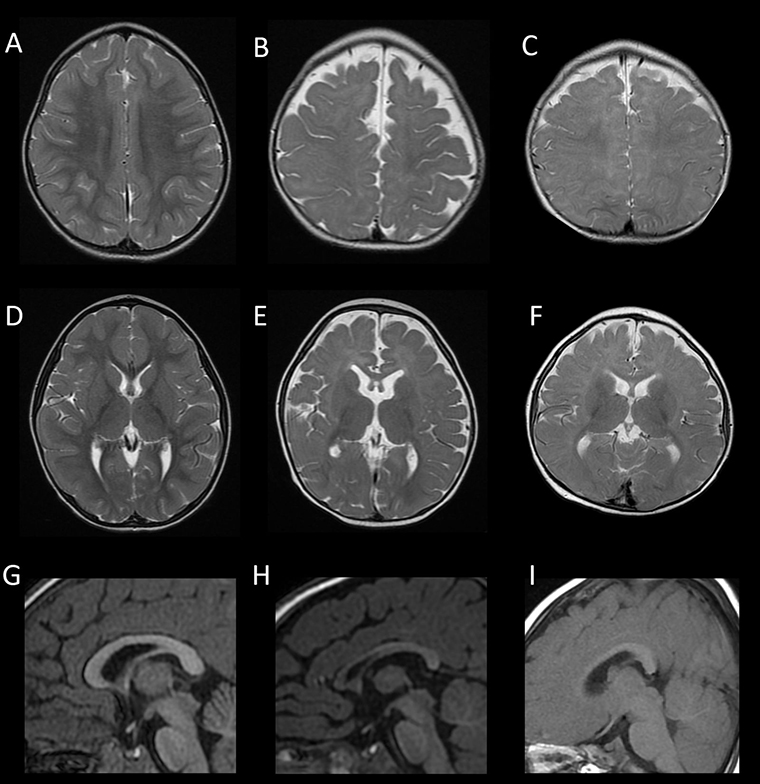

▲FOXG1症候群的腦部磁振造影。(圖/國立陽明交大腦科學研究所提供)

陽明交大腦科學研究所蔡金吾特聘教授與台大兒童醫院院長李旺祚醫師,分析來自歐洲、北美、日本與台灣等國共14名FOXG1症候群患者的臨床症狀與腦部影像資料,建立一項結合實驗室功能檢測的創新流程,包含蛋白表現分析、基因調控測試與小鼠胚胎細胞遷移實驗3種方式,成功預測超過9成病患腦部異常的嚴重程度。這項突破刊登在國際權威期刊《Molecular Psychiatry》 (分子精神醫學)。